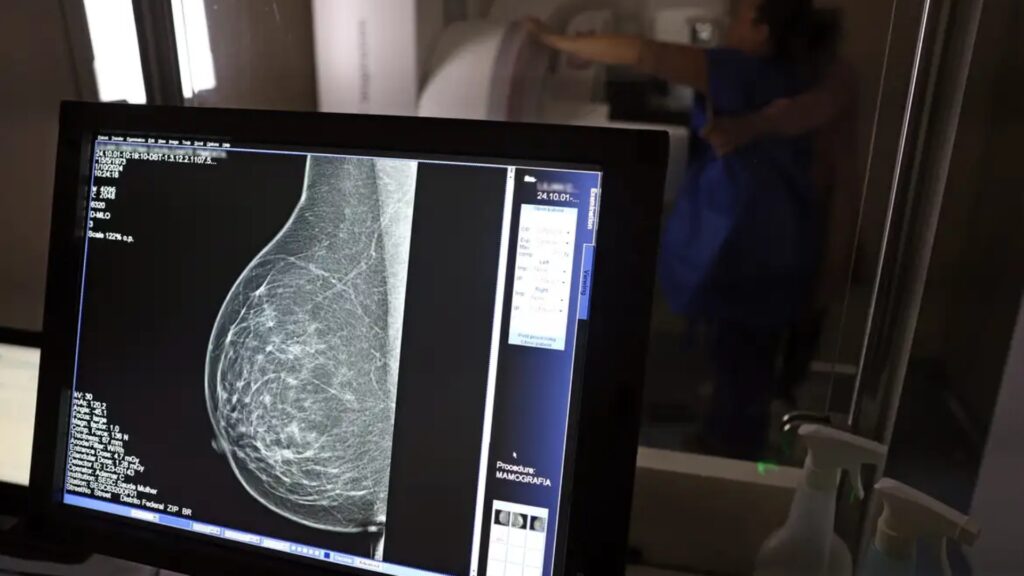

Ministério da Saúde passa a recomendar mamografia a partir dos 40 anos

FOTO: © José Cruz/Agência Brasil O Ministério da Saúde passou a recomendar o acesso a mamografia, via Sistema Único de Saúde (SUS), para mulheres de 40 a 49 anos – mesmo que não haja sinais ou sintomas de câncer de mama. De acordo com a pasta, a faixa etária concentra 23% dos casos da doença, e a […]